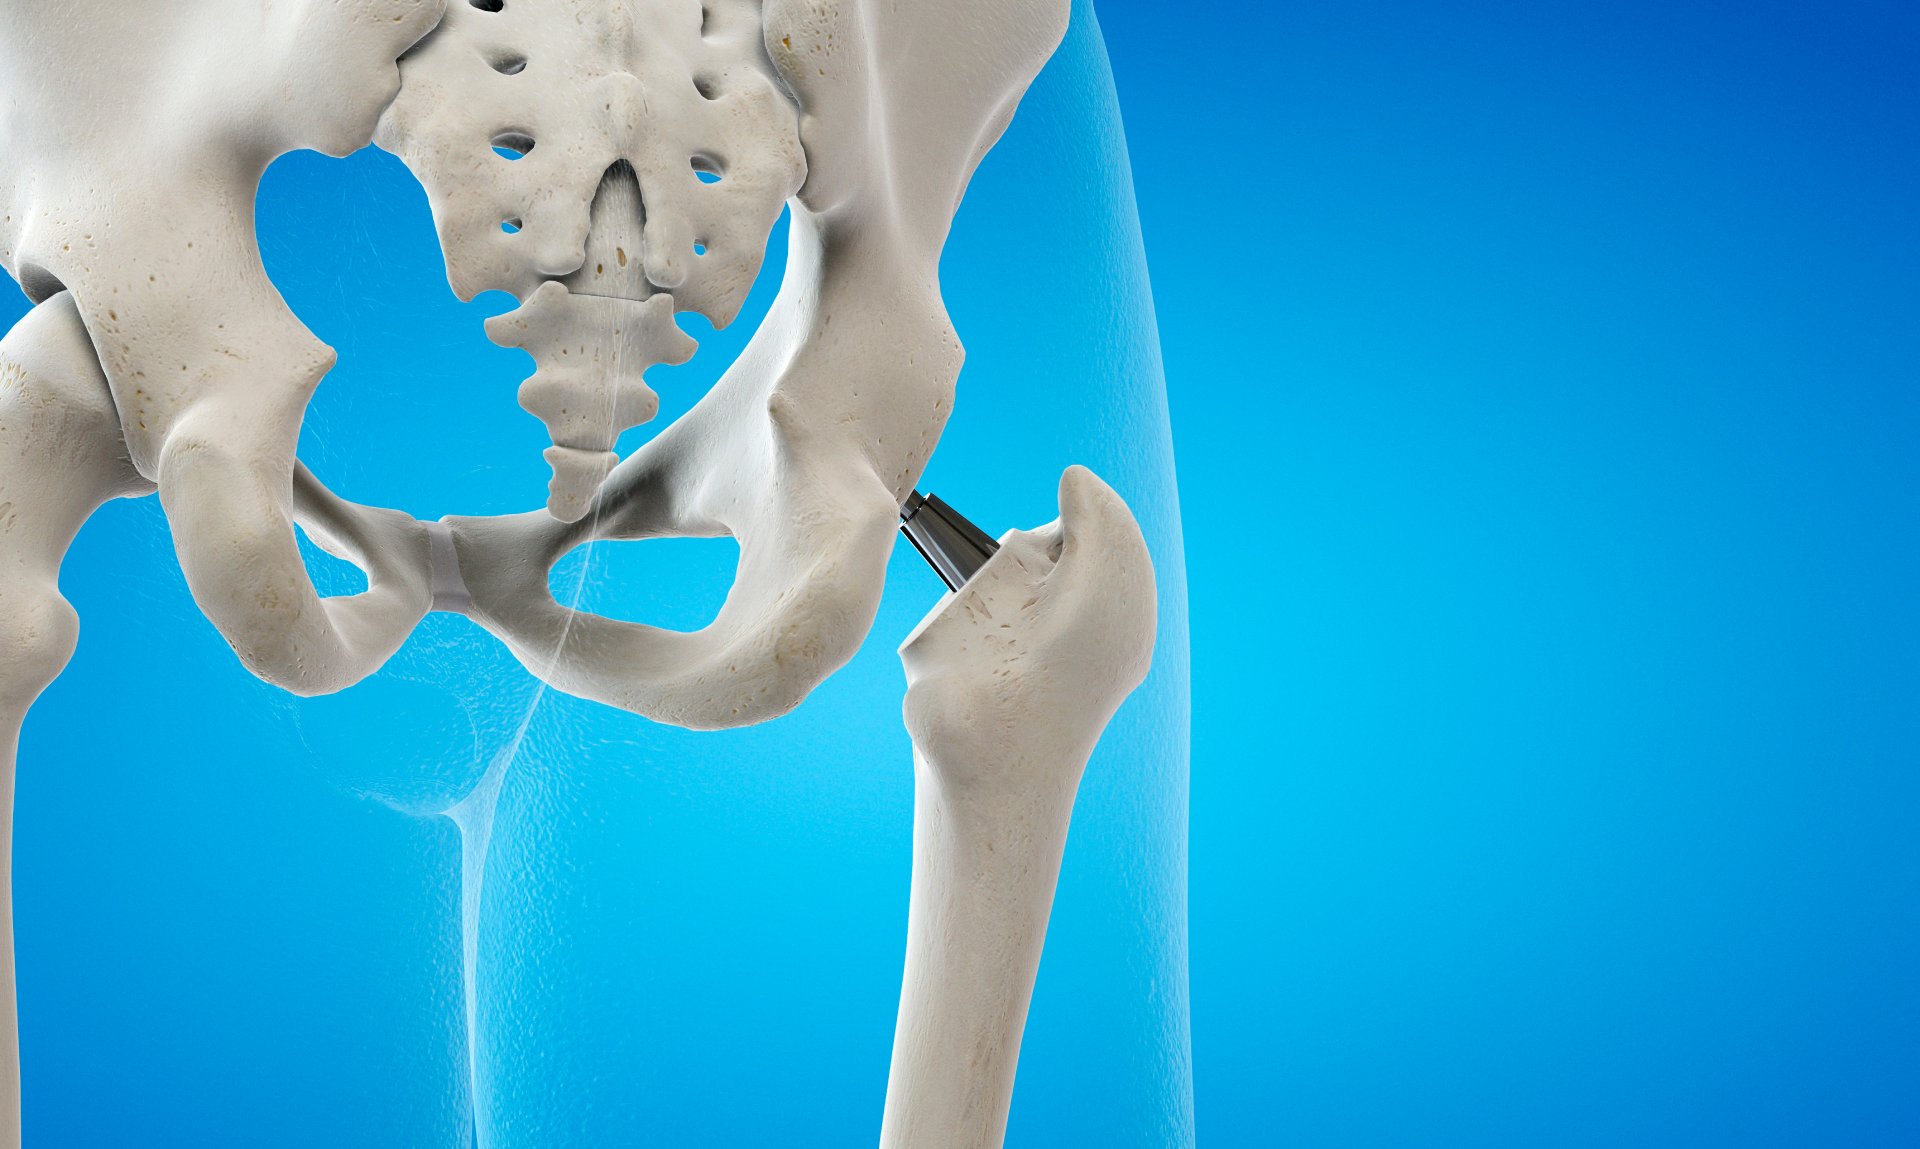

Akadnak sajnos olyan isiászos esetek is, melyekbe az ideg túlélése csak műtéti beavatkozás segítségével biztosítható, azonban ez szerencsére meglehetősen ritkának tekinthető.